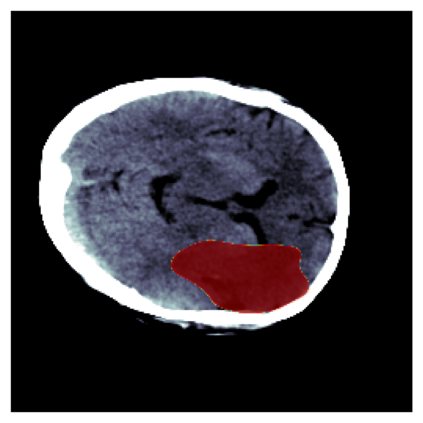

The sigmoid activation is the standard output activation function in binary classification and segmentation with neural networks. Still, there exist a variety of other potential output activation functions, which may lead to improved results in medical image segmentation. In this work, we consider how the asymptotic behavior of different output activation and loss functions affects the prediction probabilities and the corresponding segmentation errors. For cross entropy, we show that a faster rate of change of the activation function correlates with better predictions, while a slower rate of change can improve the calibration of probabilities. For dice loss, we found that the arctangent activation function is superior to the sigmoid function. Furthermore, we provide a test space for arbitrary output activation functions in the area of medical image segmentation. We tested seven activation functions in combination with three loss functions on four different medical image segmentation tasks to provide a classification of which function is best suited in this application scenario.